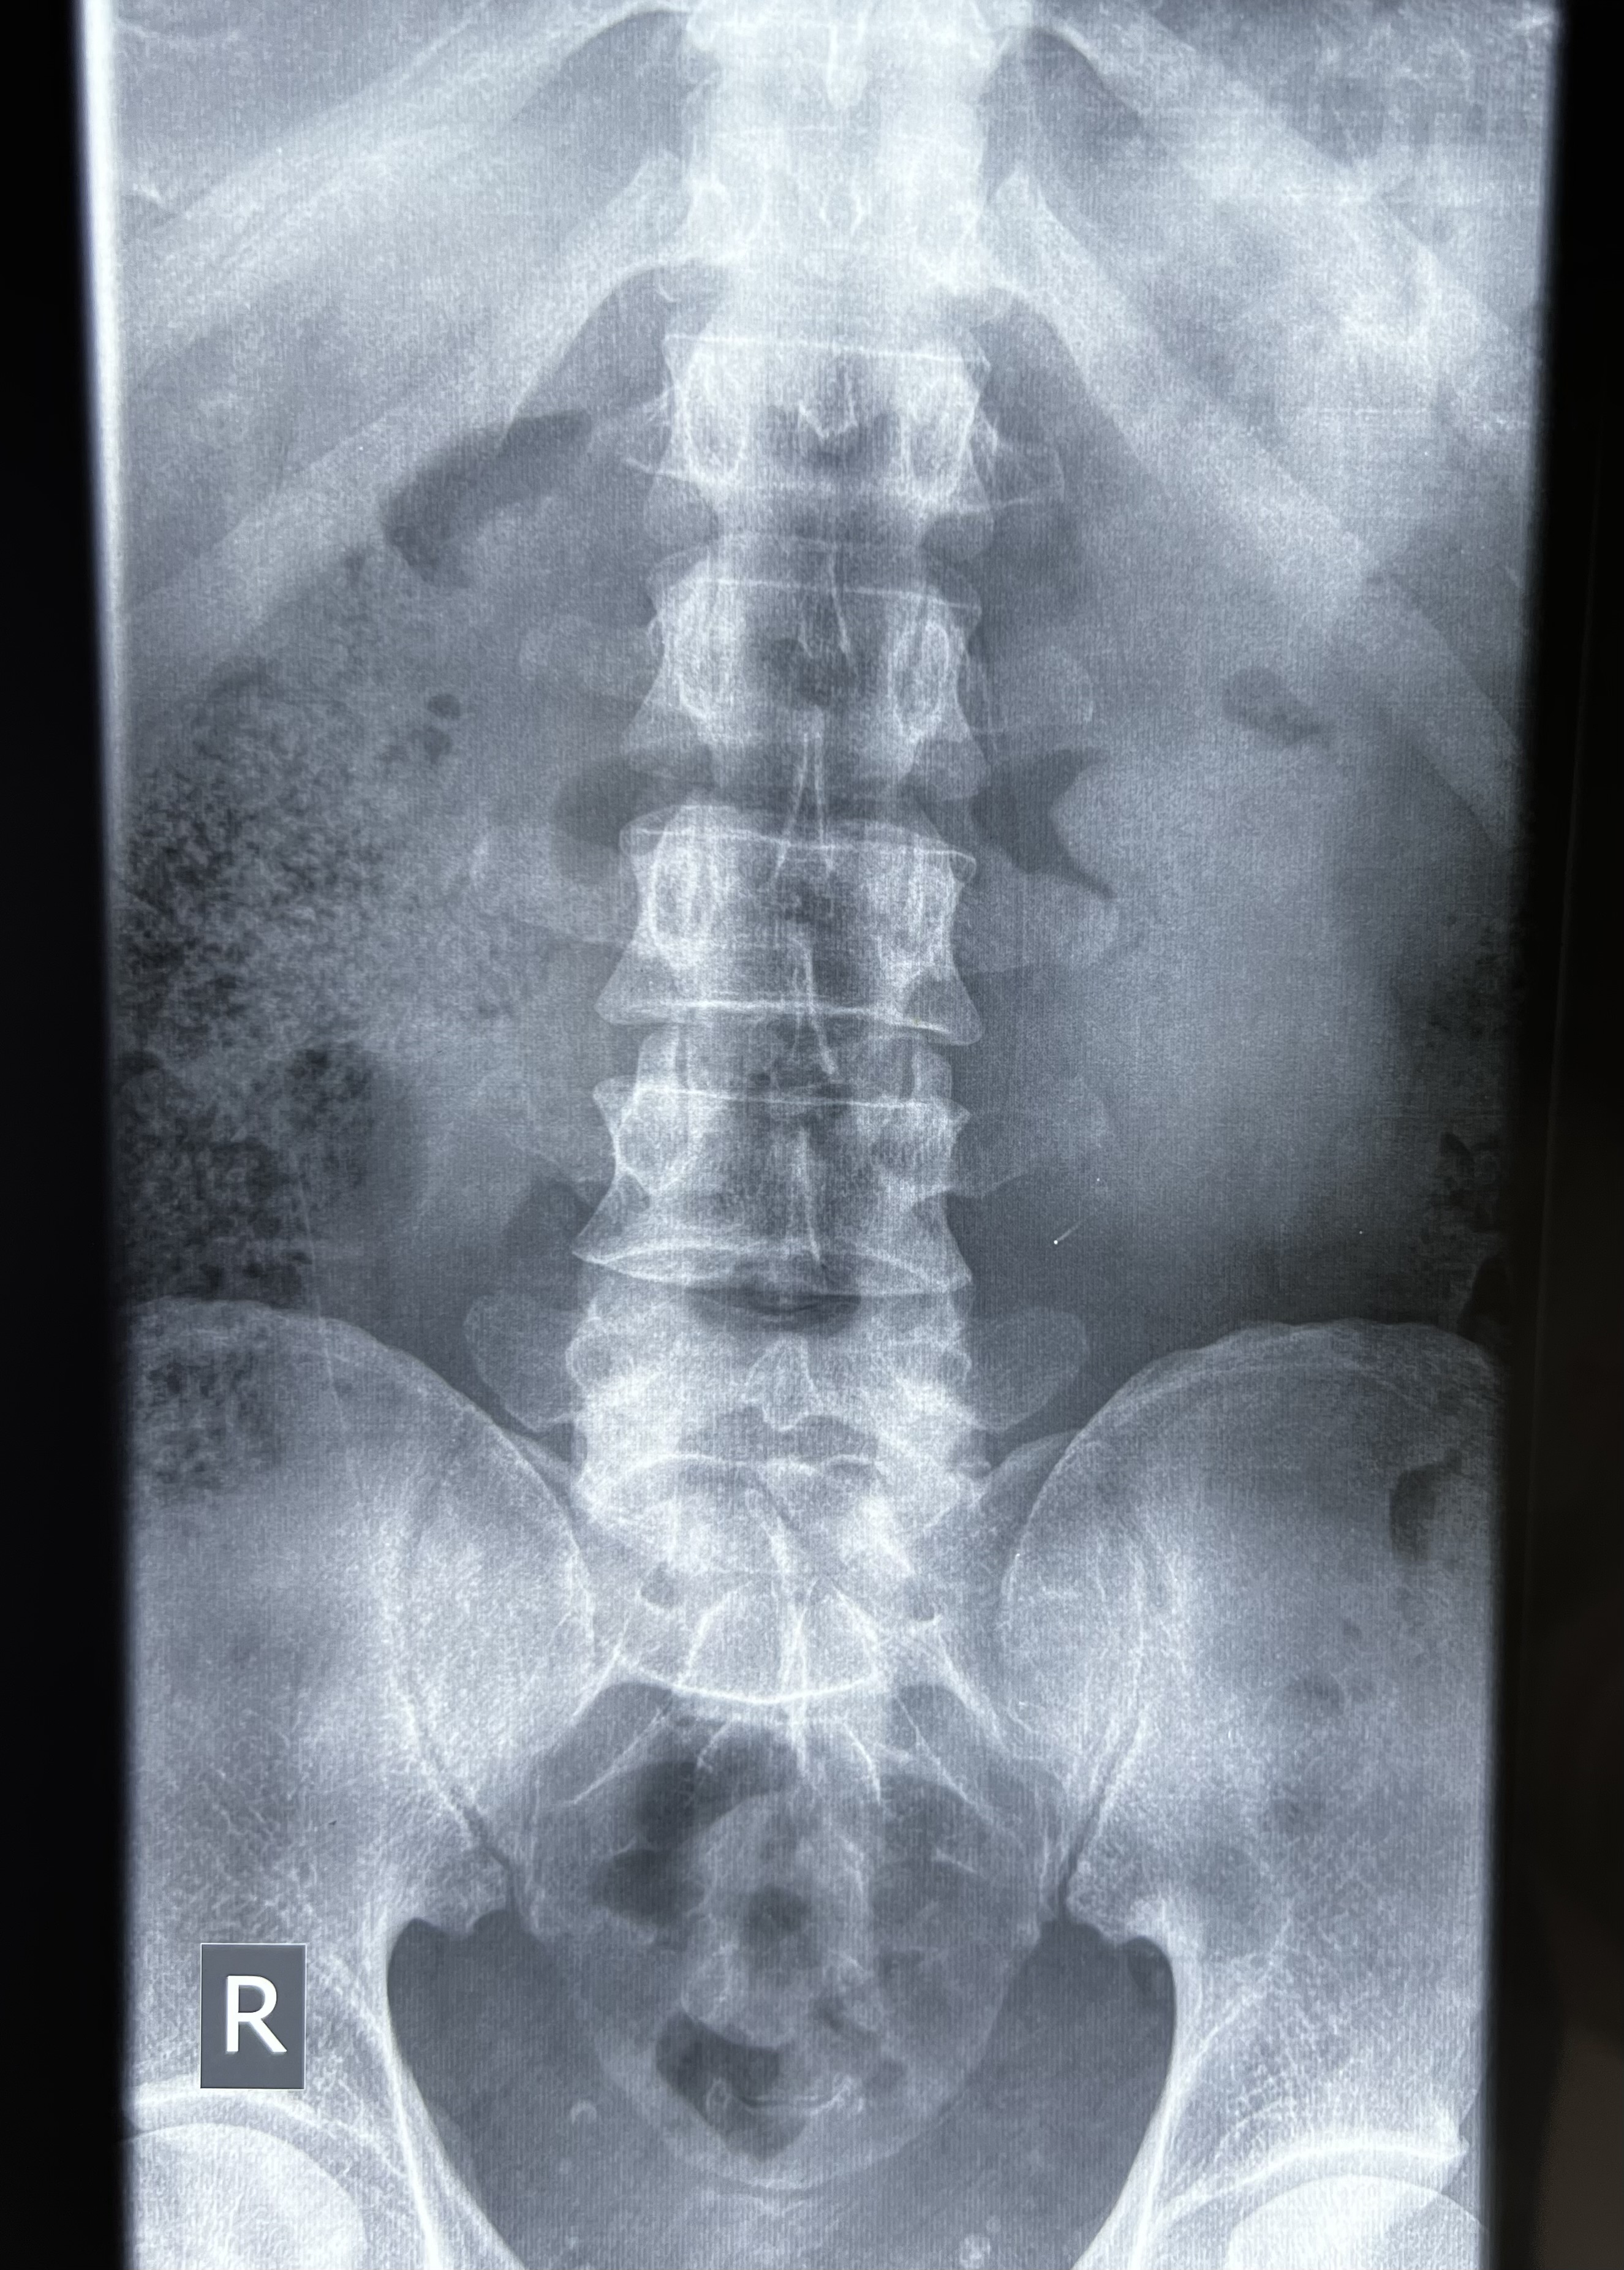

Radiology